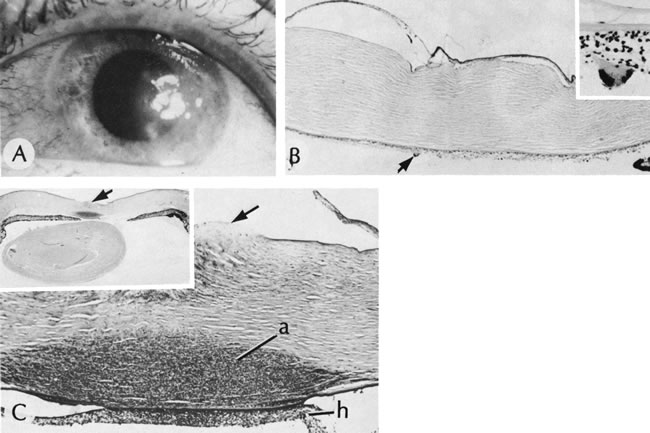

PETERS' ANOMALY

Peters' anomaly includes absence of central corneal endothelium, Descemet's membrane, and variable amounts of corneal stroma (Fig. 4). In most cases Bowman's membrane also is absent. Peters' anomaly may be caused by primary dysgenesis of the corneal endothelial mesoderm, primary dysgenesis of keratocyte and endothelial neural crest mesoderm, or secondary endothelial degeneration due to late anterior displacement of a normally developed crystalline lens.48 In addition, it has been suggested that abnormal apposition of an ectopic lens to the developing cornea during the second or third month of gestation may be the cause of exceptional cases of peripheral Peters' anomaly.49

Fig. 4. Peters' anomaly. A. Note the central corneal scar in the right and left eyes. The lens was adherent to the back of the corneal scar. Iris abnormalities also were present. B. The anterior segment shows a posterior corneal defect, a “top hat” appearance of the lens, and total adherence of the anterior surface of the iris to the cornea. C. High magnification shows termination of the endothelium and Descemet's membrane (arrow), corneal thinning, and localized absence of Bowman's membrane. The lens (lower left) is artifactually separated from the cornea. D. A PAS-positive membrane (lens capsule) is shown (top) adherent to the posterior corneal surface (arrow). The lens cortex (c) is artifactually separated from the rest of the lens (bottom). (Courtesy of SEI Photoarchives.) (B–D modified from Scheie HG, Yanoff M: Peter's anomaly and total posterior coloboma of retinal pigment epithelium and choroid. Arch Ophthalmol 87:525, 1972.)

Associated anterior segment anomalies include corectopia, iris hypoplasia, anterior polar cataract or other lens abnormalities, and iridocorneal adhesion. (Fig. 5) Corneal perforations secondary to Peters' anomaly have been reported at birth.50,51 Systemic anomalies include Potter's syndrome (agenesis of the urinary tract) and intestinal malrotation.52–54 Generally, no specific inheritance pattern has been noted, although a family that had an autosomal dominant inheritance pattern has been reported.55

Fig. 5. Peters' syndrome complicated by buphthalmos. The corneal anterior segment of the right eye has expanded because of the influence of increased intraocular pressure on scleral tissue that is still elastic in young people.

Histopathologic findings include absence of Descemet's membrane, corneal endothelium, and usually Bowman's membrane, as well as thinning of corneal stroma. The defects in Descemet's membrane, although usually single and central, may be multiple and isolated to the periphery or may be limited to an area of adhesion of iris.56 Descemet's membrane has been found to have embryonal ultrastructural characteristics combined with attenuated endothelium.57 The corneal stromal lamella are more irregular and closely packed when compared with normal. Immunohistochemical markers indicate that a normal complement of collagens type I, III, IV, V, and VI occurs in Peters' anomaly; however, an increased concentration may occur of the adhesive protein fibronectin, which is known to play a role in the embryologic development of the cornea.58–60